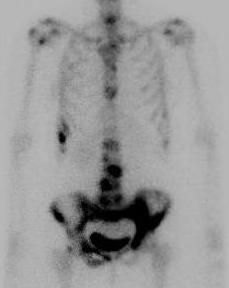

Bone Scan

1. Identify margins for resection / identify skip lesions

2. Identify metastatic disease

Bone scan with isolated disease

Bone scan metastasis